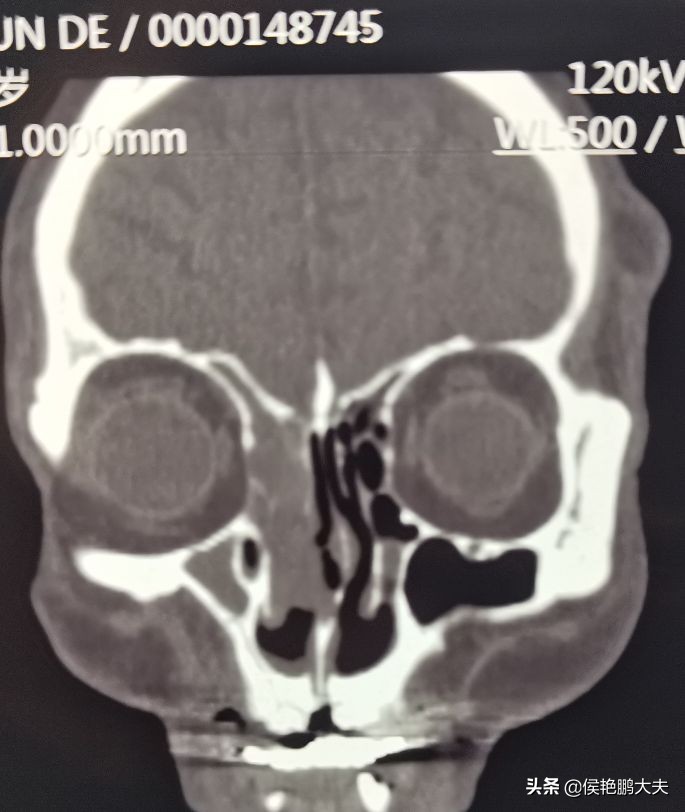

老爷子的鼻腔、上颌窦、筛窦、额窦都有软组织密度影,肿瘤根部在筛泡,侵犯到了鼻腔,上颌窦与额窦里面是肿瘤阻塞鼻窦开口而引起的感染。手术的过程很顺利,鼻内镜下彻底清除病变,开发上颌窦与额窦,清除筛房,老爷子的血压一直很平稳,手术结束后几分钟之内,他就苏醒了。